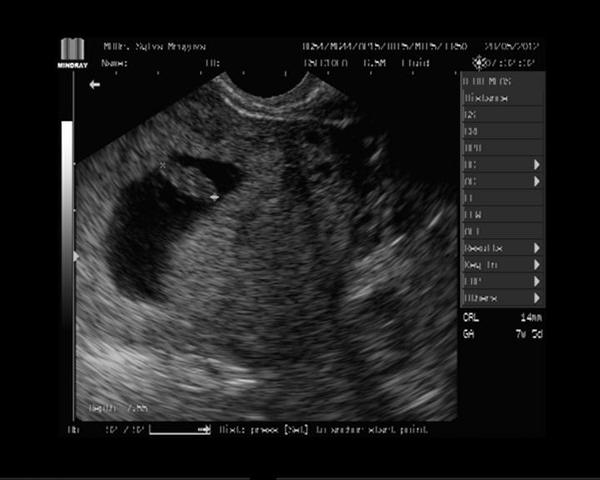

Zdravím Vás dušičky moje spřízněné,tak dnešní kontrola dopadla na jedničku.Fazolka roste jak má 7+5tt,14mm a srdíčko buší 🙂.........................Na obávanou kontrolu jdu 8.6.,tak snad už to do třetice bude jak má být a srdíčko nepřestane bušit!!!............................Jinak myslím na Vás berušky stále a přeji jen to nej nej nej 🙂